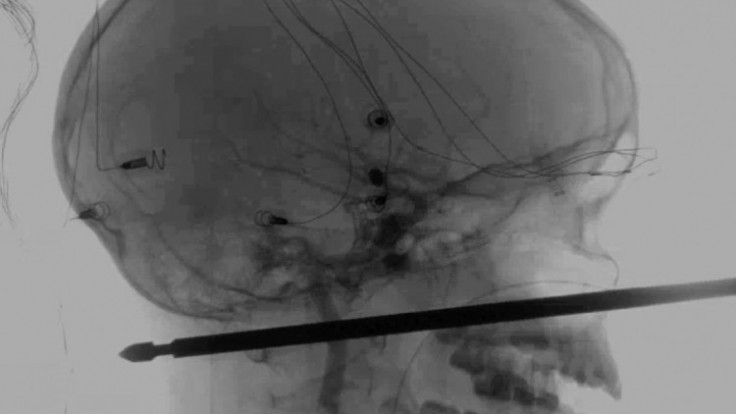

Desaťročný chlapec z amerického štátu Missouri sa zotavuje po tom, ako naňho zaútočil hmyz a zrútil sa zo stromu na zem, kde dopadol na kovový ražeň na mäso a ten mu prepichol lebku cez tvár až do zadnej časti hlavy.

Denník napísal, že lekári označili prežitie Xaviera Cunninghama za "zázrak". Xavierov hrozivý zážitok sa začal, keď naňho v domčeku na strome v rodinnej záhrade v meste Harrisonville zaútočili sršne. Chlapec spadol na zem, a keď jeho matka počula výkriky, rozbehla sa za ním. Lebku mal spredu dozadu prebodnutú polovicou 30-centimetrového kovového ražňa, ktorý mu stále trčal z tváre.

Šéf oddelenia neurochirurgie Lekárskej fakulty Univerzity v Kansase Koji Ebersole vyhlásil, že odstránenie ražňa v nedeľu nebolo jednoduché, ale ražeň minul Xavierovo oko, mozog, miechu aj hlavné cievy.